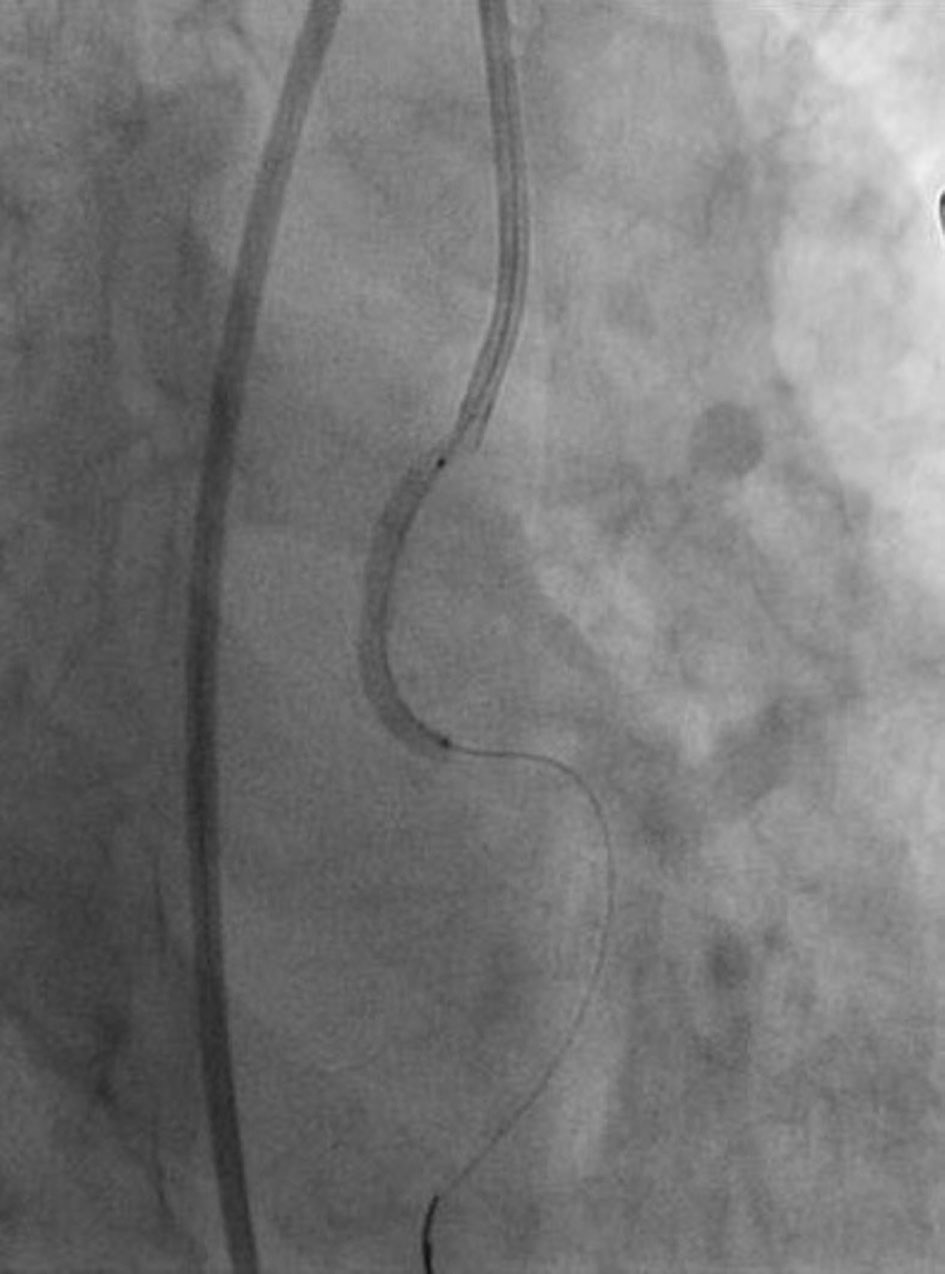

A 49-year-old female with a past history of diabetes mellitus, hypertension, and dyslipidemia presented with retrosternal chest pain and sweating of 3 h duration. Her physical examination and biochemistry were all unremarkable. Echocardiography revealed mild hypokinesia in LCx territory with ejection fraction of 55%. Electrocardiogram revealed ST-elevation in II, III, and aVF and reciprocal changes in I and aVL. She was taken for primary percutaneous coronary intervention (PCI) through femoral route after proper consent. She was preloaded with prsugrel 60 mg, aspirin 325 mg and atorvastatin 80 mg. The 6 F JR3.5 and JL3.5 ProfloTM diagnostic catheters (Medtronic, USA) were used for catheterization after administering 2,500 U of heparin. Angiogram of left system revealed plaque in distal left main, critical lesion in proximal left anterior descending (LAD) artery and normal obtuse marginal branch (Fig. 1). Right coronary artery (RCA) was uneventful showing a smooth, normal coronary artery (Fig. 2). We started looking for LCx as it was incompatible with diagnosis. On gradual pullback of JR diagnostic catheter, LCx was seen arising from RCA ostium showing tubular lesion with 90% stenosis in proximal segment (Figs. 3 and 4). Therefore, angiogram revealed a double LCx: one arising from left and the other originating from RCA ostium. PCI was planned of the culprit artery only and 7,000 U of heparin was given further. As a 6 F JR3.5 guiding catheter (Medtronic, USA) was deeply engaging RCA similar to diagnostic one, it was improvized by slightly straightening its tip (Fig. 5) and LCx was cannulated with counterclock twist (Fig. 6). Amplatzer catheter (AL) was avoided to prevent ostial injury to RCA and double jeopardy in form of injury of RCA and LCx. As support was not adequate, two balance middle weight (BMW) guidewires 0.014″, 190 cm (Abott, USA) were parked beyond the lesion, second acting as buddy wire (Fig. 6). Lesion was pre-dilated with 2 × 10 mm Minitrak balloon (Abott, USA) to 12 atm (Fig. 6). After positioning the stent, buddy wire was pulled into the guiding. Lesion was stented by deploying 2.75 × 33 mm Xience Prime stent (Everolimus drug-eluting stent, Abott, USA) up to 13 atm pressure (Fig. 7) and further post-dilated by 2.75 × 10 mm Minitrak non-compliant balloon up to 24 atm (Abott, USA) achieving TIMI 3 flow in LCx (Figs. 8 and 9). Her symptom and ECG were stabilized. The patient was discharged on the following day with aspirin 150 mg/day, prasugrel 10 mg/day, atorvastatin 80 mg/day, metoprolol 100 mg/day and ramipril 2.5 mg/day. Patient is doing excellent since then with regular follow-up at our institute.

![]() Click for large image | Figure 5. Improvization of Judkins right catheter by straightening its tip. |